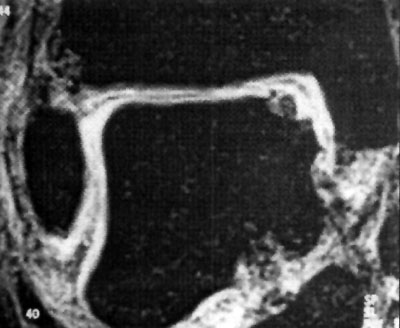

Foto 1: lesión anterolateral

Foto 2: lesión posteromedial.